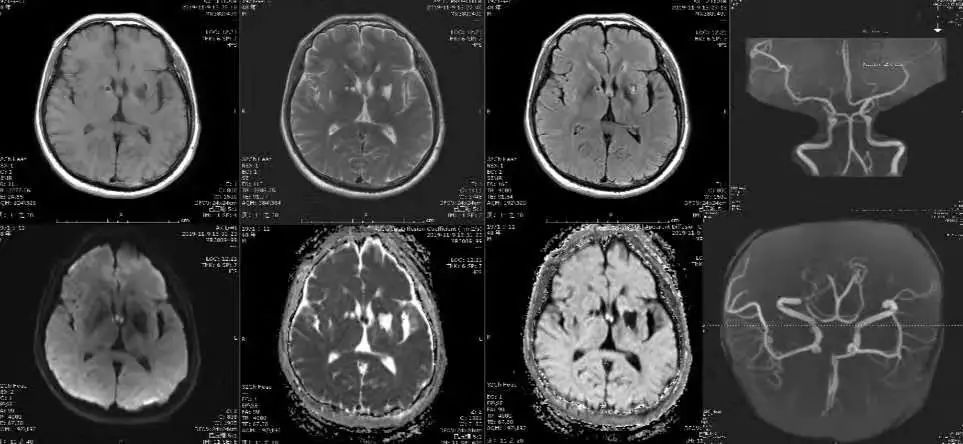

男性,66岁,记忆力进行性下降2天。

答案:Percheron动脉梗死。

法国神经病学家Percheron认为,丘脑穿通动脉有4种解剖类型:Ⅰ型,丘脑穿通动脉起自同侧PCA P1段,绝大多数属此类;Ⅱa型,丘脑穿通动脉均起自一侧PCA P1段;Ⅱb型,丘脑穿通动脉单一主干起自一侧PCA P1段,并分支供应双侧旁正中丘脑;Ⅲ型,丘脑穿通动脉起自PCA P1段后形成“桥动脉”,并分支供应双侧旁正中丘脑。Percheron动脉特指Ⅱb型。由于Percheron动脉同时供应中线旁双侧丘脑及中脑上部,所以该动脉闭塞后可引起双侧丘脑及中脑梗死。但由于存在其他动脉分支提供中脑上部供血,故中脑也可不受累及。